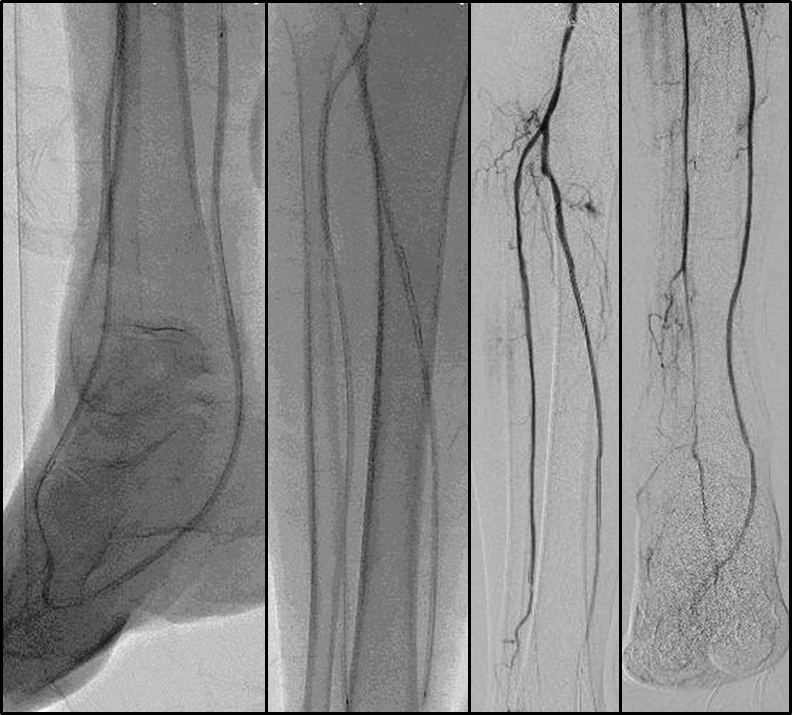

针对BTK病变,可采用多种腔内技术:

01

顺行技术

Knuckle/ADR(Antegrade Dissection and Re-entry)

02

逆行技术

Trans-luminal

From no-target artery

Through pedal arch or ACA/PCA

To distal cap of CTO in target artery

Transcutaneous

Surgery exposure

Puncture

在操作中需遵循两大核心原则:

ALARA原则:在保证疗效的前提下,尽可能降低辐射剂量和造影剂用量。

区域化操作策略:

平直区域:可快速通过(真腔或内膜下);

关键区域(如CTO开口、出口、BTA区域):必须谨慎操作,避免穿孔等并发症。